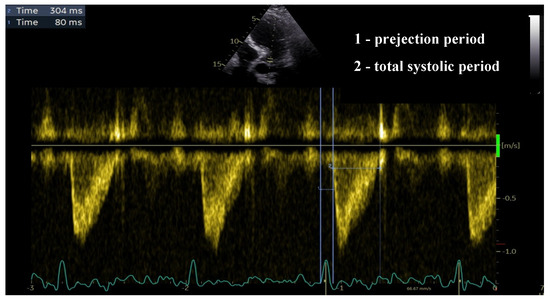

| tND | ratio of the pre-ejection period to the total systolic period measured on the aortic pulse |

− 159.1 × tNd7